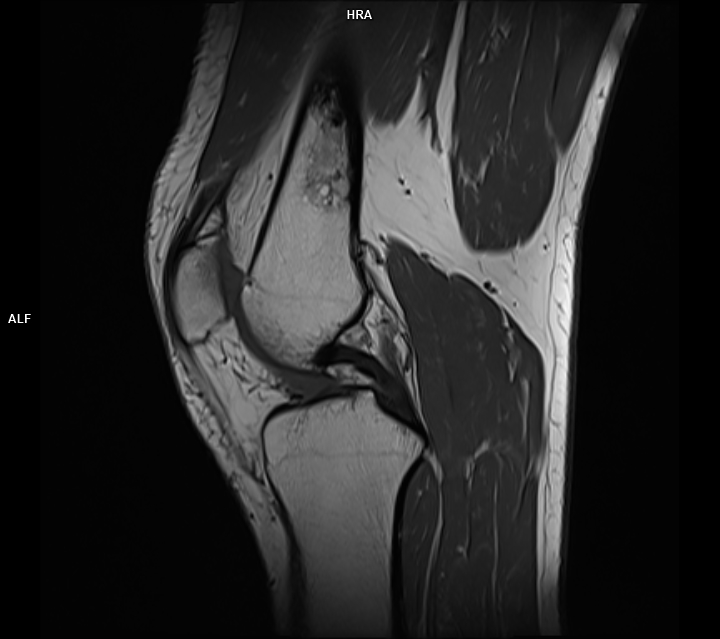

Figura 2, 3: achiziție T1 sagital